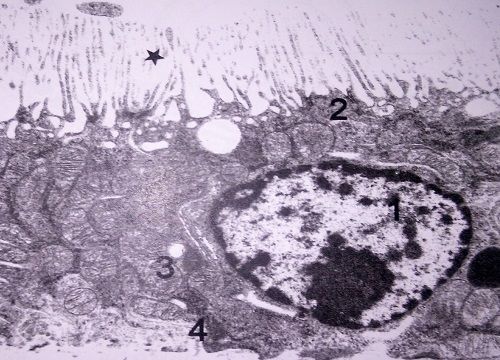

Question 29

Question

Label this image

Image:

c7eb4b5b-3919-4bcc-b8d6-d3c1a6cce9f2 (image/jpeg)

Answer

Blood Urinary Barrier